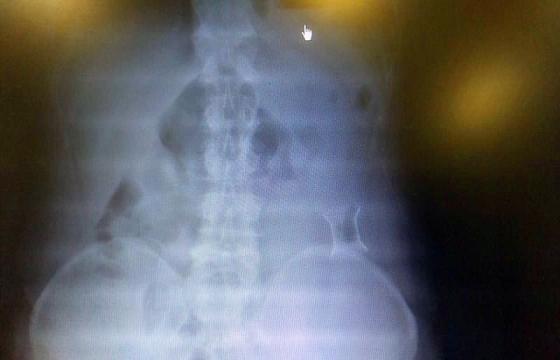

受試患者在結腸端端吻合術中,使用我司新研制產品達到了理想的預期效果。患者術后7天、14天X光片顯影,可降解腸道支架均能按研制設計的預期時間節點保持應有強度,術后21天X光片顯示可降解腸道支架已完全破碎,并排出體外。在整個試驗過程中,病患無任何不良反映,耐受良好。